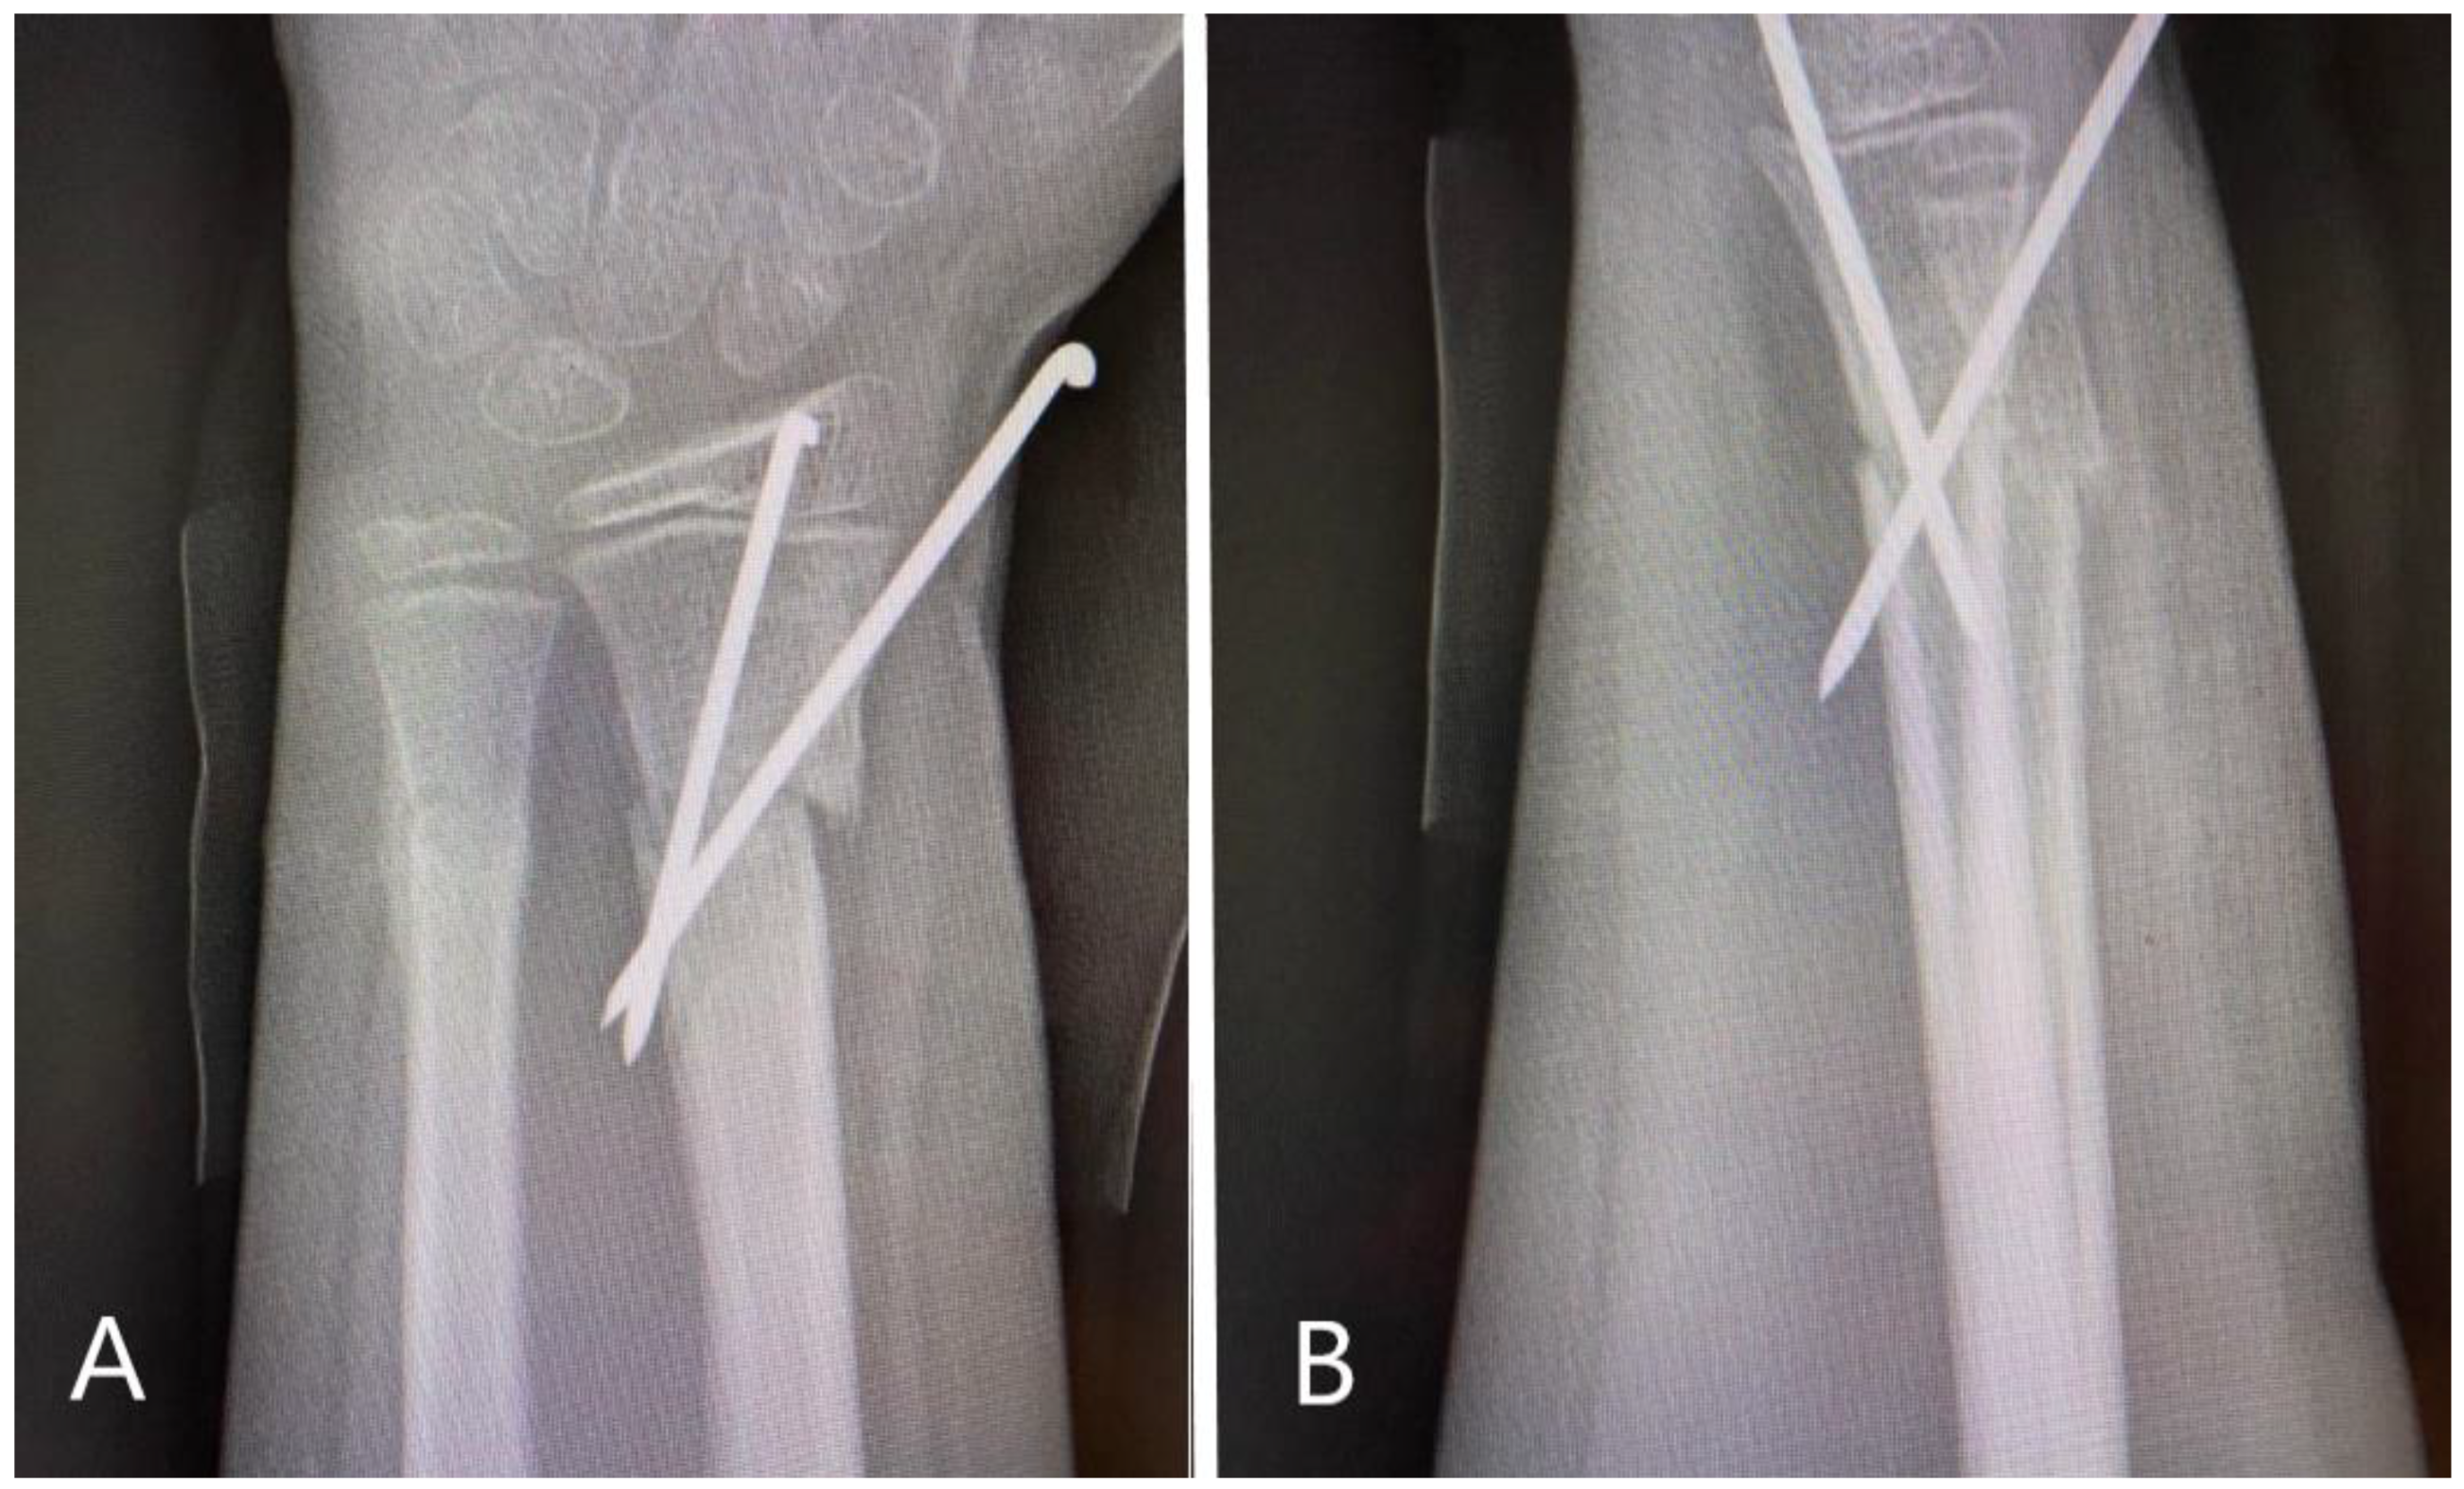

Due to the fact that orthopedic maneuvers were not efficient, the patient was taken to the operating room and the maneuvers repeated under general anesthesia, but this was also inefficient. A mini open reduction technique was applied, in which a K-wire was introduced into the fracture site through a <1 cm skin incision and used as a lever to facilitate reduction. Once reduction was obtained under fluoroscopy, the fracture was fixed percutaneously using two crossed K-wires, obtaining satisfactory stability and the final result (Figure 2).

Figure 2. Radiological images obtained post-operatively. (A): AP view of the distal forearm, demonstrating good reduction of the fractures and fixation of the radius with two crossing K-wires according to AO pediatric technique. (B): Lateral view with very good reduction of the volar angulation of the radius, with slight but acceptable displacement of the ulna.